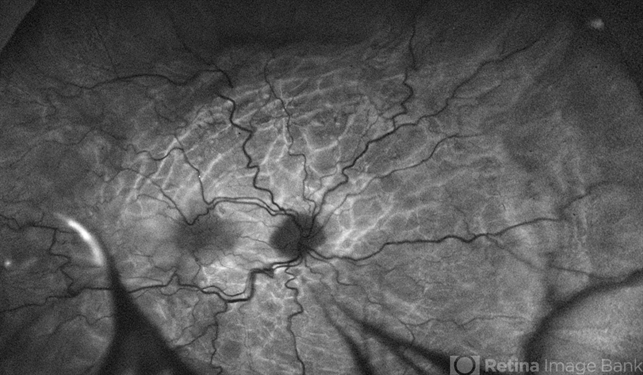

- fundus autofluorescence (FAF), choroidal folds, hypotony maculopathy, hypotonous retinopathy, choroidal detachment

- Fundus autofluorescence image of 81-year-old male with right eye ocular hypotony due to leaking bleb. Note severe hypotony maculopathy, peripheral choroidal detachments, multiple chorioretinal folds.